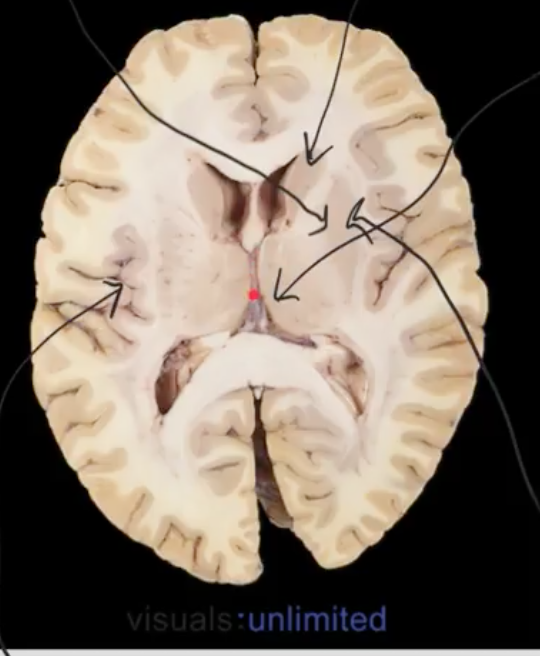

what is red dot? why is it squashed

3rd ventricles, due to the thalamus on either side!